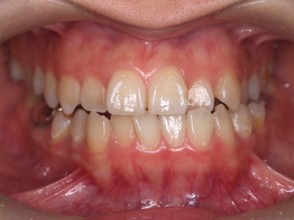

外科矯正治療・インプラント治療の症例紹介(三隅歯科クリニック)

症例詳細

| 主訴 | 20代女性 矯正治療希望。治療途中の歯もあるので治したい。左顎関節が痛い。 |

| 治療内容 | 矯正治療を行いました。 |

| 治療費 | 1,400,000円(税込み) |

| 治療期間 | 3年(矯正治療期間 2年半) |

| 治療回数 | 40回 |

| 想定されたリスク | 顎骨の変形があったので、全身麻酔下による外科処置が必要になり、身体的、精神的負担が増す可能性がありました。 清掃状況によっては矯正中にむし歯が発生するリスクがありました。 |